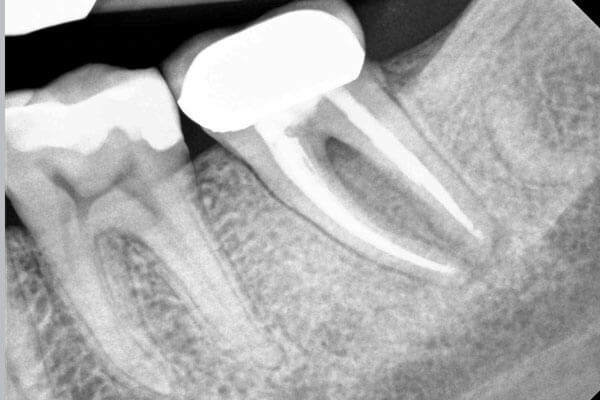

A root canal is a common procedure recommended when a tooth is badly infected. This can happen when the pulp inside a tooth becomes infected with bacteria. An untreated cavity, injury or crack in the tooth can cause this.

Before we begin, we’ll apply anaesthetic to the teeth, gums, and surrounding skin to numb the entire area. Our dentist will remove bacteria, the damaged nerve, and the pulp inside the tooth.

Once all the damaged and infected material has been removed, the chamber will be thoroughly cleaned and dried to reduce the risk of further infection.

The next step is to fill the tooth chamber and seal it.